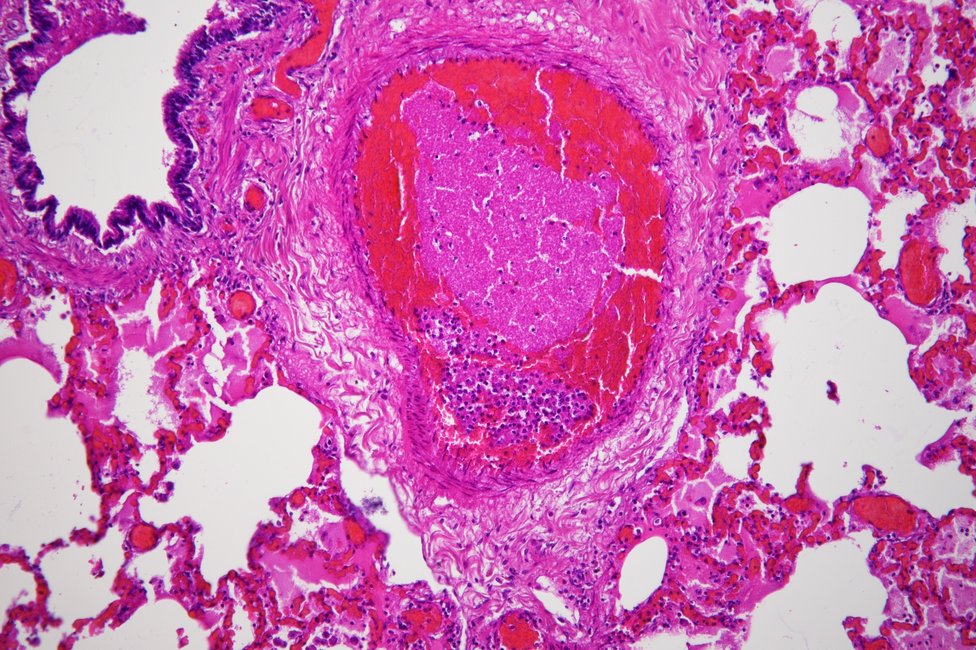

Forensic histology assumes an essential role in the context of forensic post-mortem examinations, since specific histochemical and immunohistochemical staining methods can be used to detect statements about the cause of death, e.g., early organ damage caused by oxygen deficiency, but also to determine the age of injuries and to perform vitality tests.